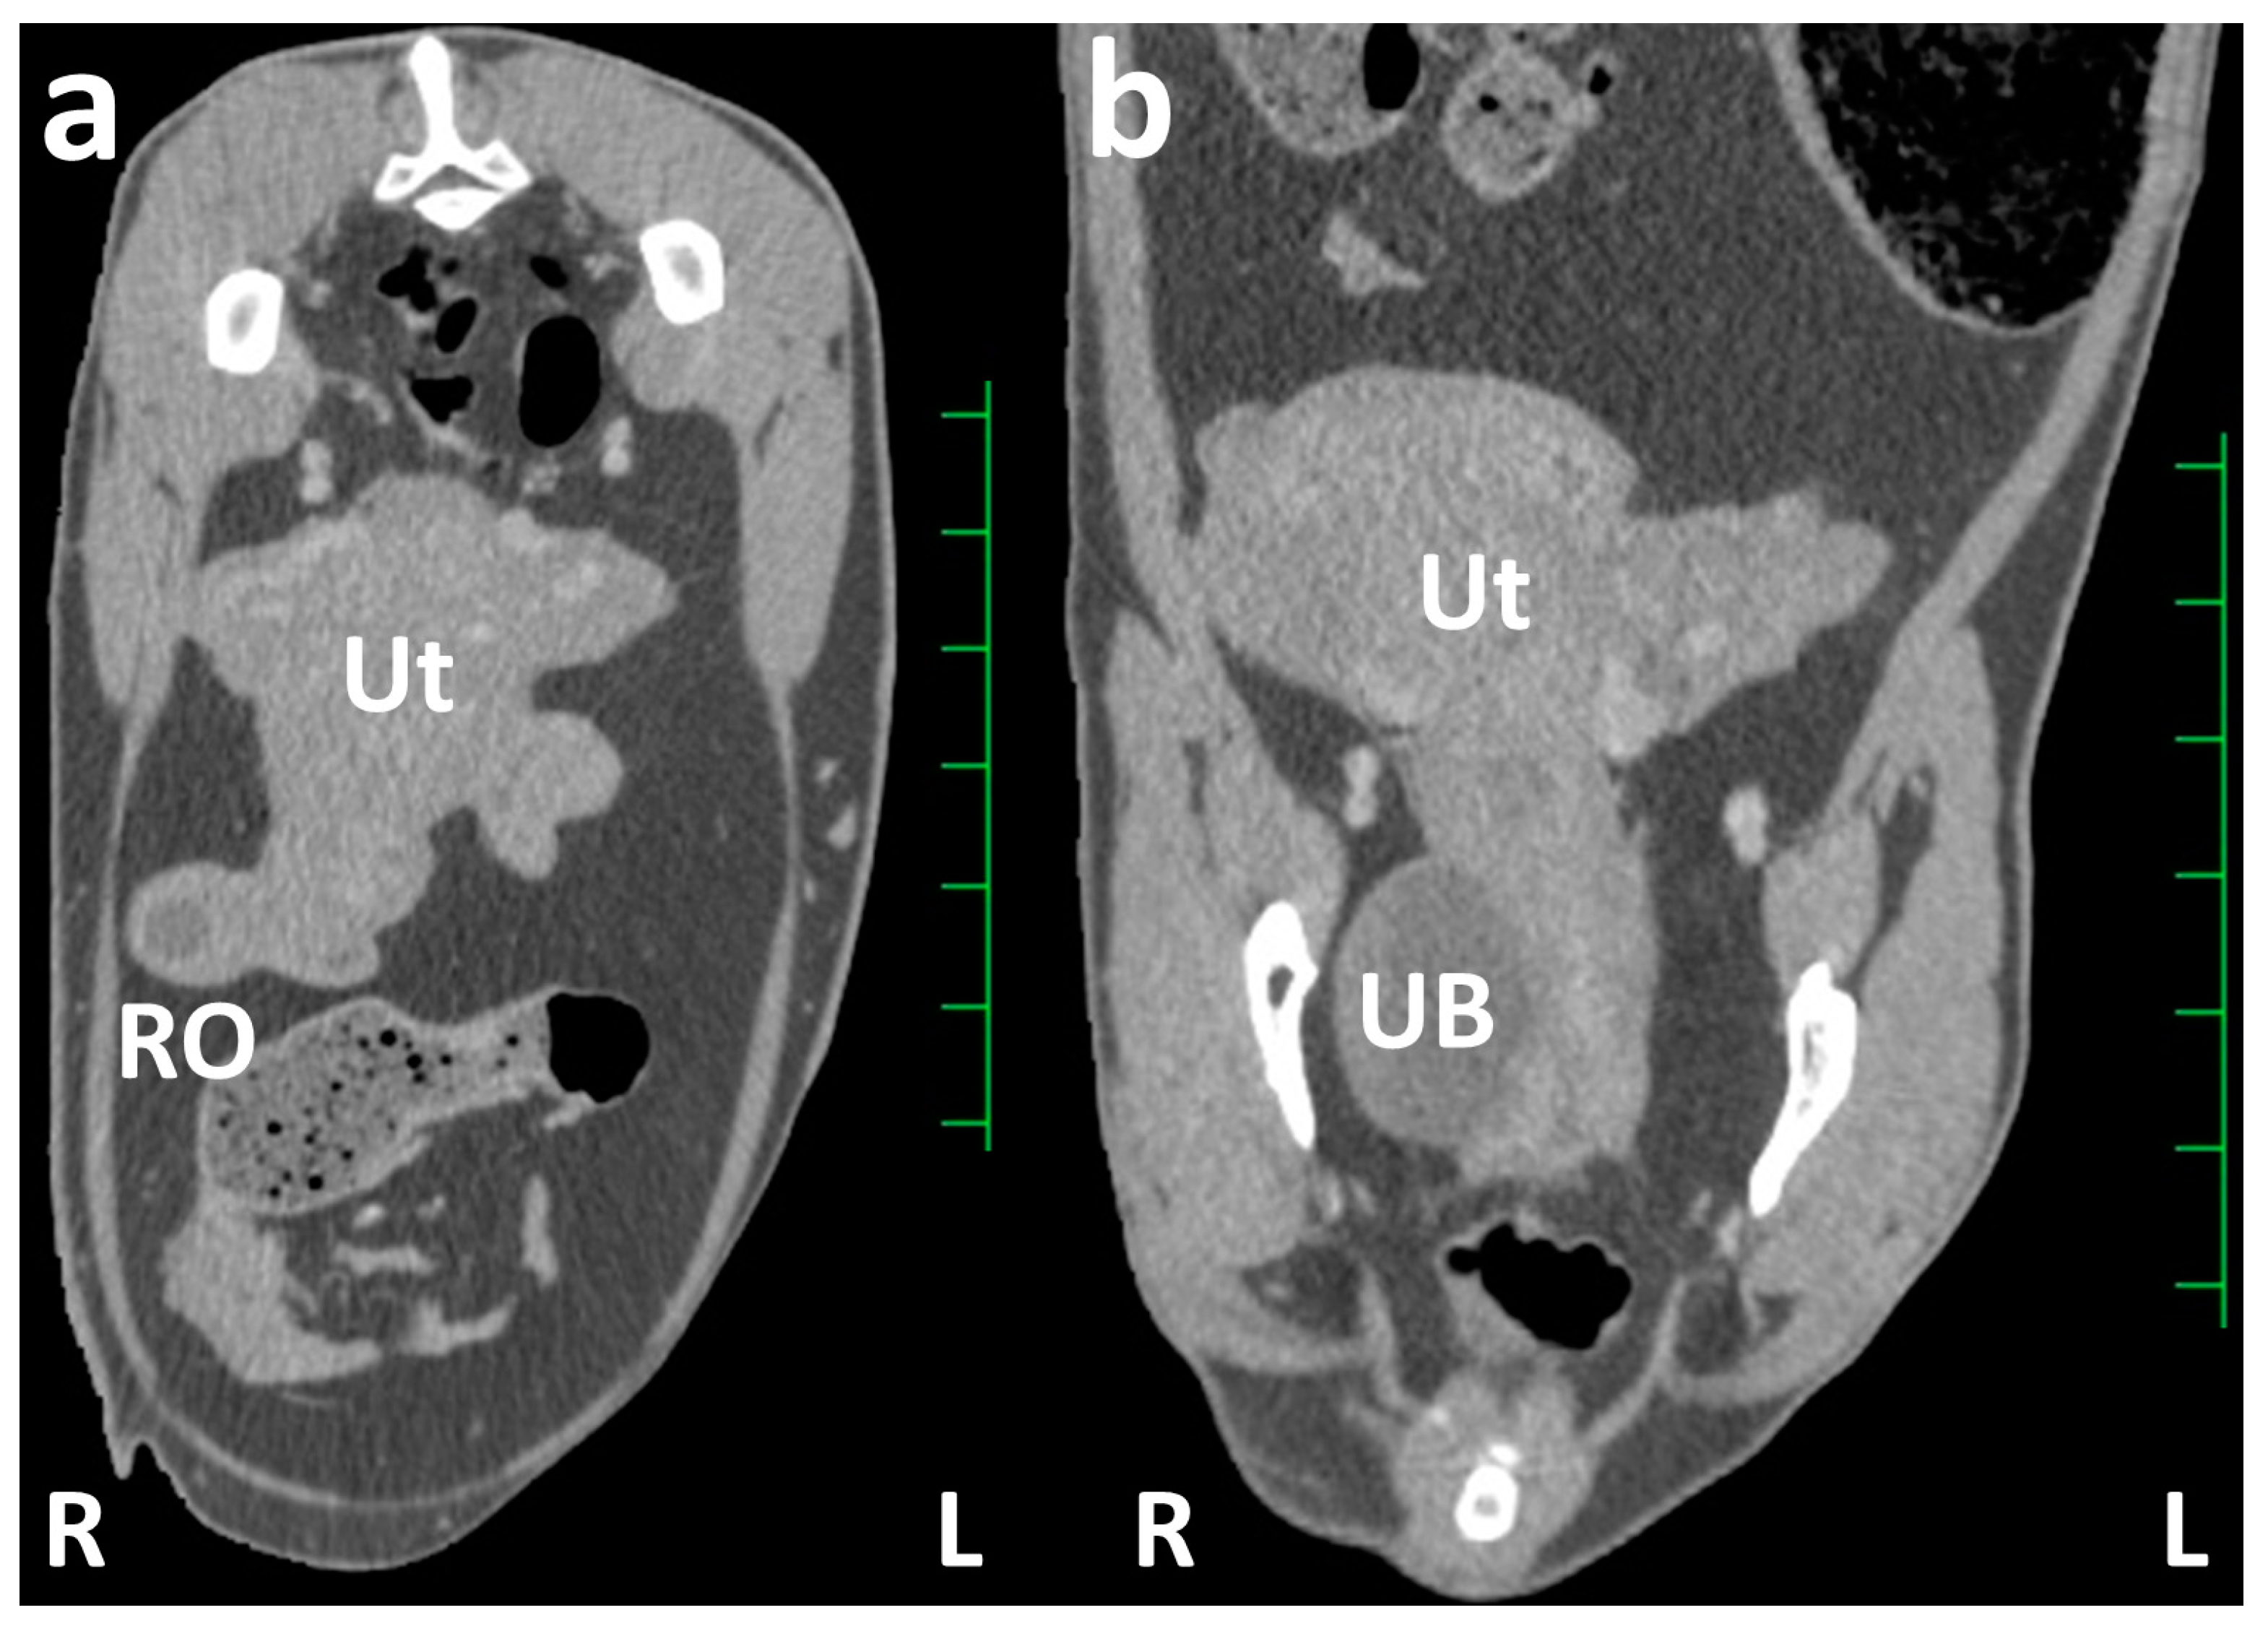

CT: The animal was examined using a slip-ring CT scanner (Pronto SE; Hitachi Co. Ltd., Tokyo, Japan) while positioned in the lateral recumbency on the examination table under anesthesia after intravenous injection of xylazine hydrochloride (0.2 mg/kg; Selactar 2%; Bayer Yakuhin Ltd., Osaka, Japan). The transverse CT images obtained from scanning after intravenous injection of the contrast medium, iopamidol (2.0 mL/kg; Iopamirone 300mg/mL; Bayer Healthcare, Osaka, Japan), displayed a heterogeneously enhanced uterine mass. In this uterine mass, the right uterine horn appeared as a ball-like structure of approximately 5 cm in size at the basal area, and the uterine tube was also enlarged to a thickness of approximately 2 cm (Figure 2a). The lumen of the enlarged right uterine horn and uterine tube was unclear on the CT. The right ovary was approximately 2 cm in size and included a non-enhanced, round, follicle-like structure of a maximum of 10 mm. The left uterine horn was enlarged to a thickness of approximately 3 cm. The structure of the left ovary was not evident on CT because it overlapped with the structure of the uterine horn. On the dorsal CT section of the caudal abdomen, the right uterine horn was thicker than the left (Figure 2b). No morphological or contrast-enhanced abnormalities were observed in other abdominal organs. No lymphadenopathy was evident in the abdominal cavity.

Figure 2.

Transverse (a) and dorsal (b) contrast computed tomography images of the caudal abdomen. (a) The right uterine horn is shown as an enlarged, round structure, larger than that of the left uterine horn. The homogenously contrast-enhanced structure represents the enlarged uterus (Ut), wherein the uterine lumen is unclear. The contrast-enhanced ball-like structure of the right ovary (RO) includes a round cystic structure with weak contrast enhancement. (b) The uterus (Ut) is represented as the enlarged uterine cervix running along the urinary bladder (UB) within the pelvic cavity, and the uterine horns extend to the location approximately 4 cm cranially compared with the pelvis. Scale = 25 mm.

Previous clinical use of CT for diagnosing caprine urogenital diseases has rarely been reported [24,25], despite a few previous reports describing the anatomical evaluation of abdominal CTs in goats [20]. In the CT scans of the caudal abdomen and pelvis, where the narrow cavities are fully crammed with the reproductive tract, the urinary system, colon, and rectum can be identified as separate structures without an overlap in two-dimensional CT sections [20,37]. CT can provide basic transverse cross-sectional images, enabling the reconstruction of every directional plane and a three-dimensional image [20,37]. Reconstructed sagittal CT planes can contribute effectively to evaluating the extent of masses that spread between the abdominal and pelvic cavities and the positional relationship of pathological uterine and ovarian structures against the peripheral organs [25,38]. Detecting the systemic formation of metastatic foci and lymphadenomegaly during whole-body scanning using CT can lead to diagnostic suggestions for neoplastic lesions [24,25]. The CTs of reproductive tract lesions can be evaluated quantitatively by measuring lesion size and Hounsfield units [37]. In the present case, the CT-based measurement of ovarian follicle size within the right ovary helped diagnose a follicular cyst based on the ultrasonographic criteria of follicular cysts [3,7,11,21]. These cysts were >10 mm in size [3,7,11,21], compared with 8–9 mm of the maximum size of a follicle formed within the ovary in the estrous cycle of female goats [11,18]. Contrast techniques for radiographic examination are applicable to CT scanning [25,38,39]; these techniques include excretory urography, retrograde cystography [38], hysterography, identifying the pathological enlargements of the affected uterus and fertile states [14,16], and vaginography, helping in diagnosing ectopic ureters and urethrovaginal and rectovaginal fistulas [15,39]. The intravenous injection of contrast medium during CT scanning can provide significant evidence of contrast enhancement, such as the difference in contrast-enhanced density within the lesions and the time required for contrast enhancement [24]. Contrast enhancement and fluid retention within the uterine lumen are significant CT features that differentiate between neoplastic and non-neoplastic uterine diseases [25]. In the present case, contrast CT revealed that the thickened uterine walls were occupied predominantly by a fluid retention area within the enlarged uterine structure.